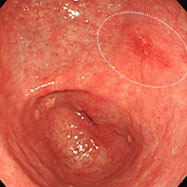

通常観察ではわずかに発赤しているのみですが、

NBIモードにすることで境界がはっきりし、わずかに凹凸していることもわかります。

通常観察では平坦な発赤として認められます。

色素を散布することにより、境界がはっきりしました。